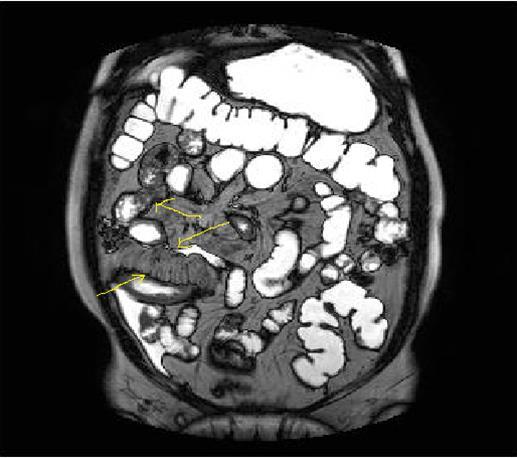

Figure 3a-3b-3c.Diffuse mucosal involvement and extreme luminal narrowing in the terminal ileum due to Crohn’s disease on T2W coronal sequence after OCA administration, stricture and string sign near ileo-ceccal valve in Figure 3b.